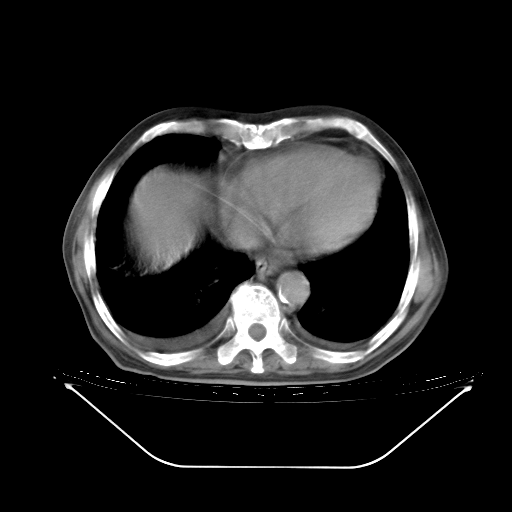

今天复查肺部CT,发现双肺广泛磨玻璃样改变。所以我把3月19日和5月9日相隔50天的肺部CT上传。请大家会诊。

5月9日肺部CT(在4月27日齐鲁医院肺部CT描述部分肺组织磨玻璃样改变,12天后肺组织广泛磨玻璃样改变)

2009年5月9日肺部CT

大致读了系列胸部CT:纵隔窗无明显异常,肺窗:从4、27至今:主要是双肺中下野外带可见毛玻璃样改变,目前处于急性肺泡炎阶段,至于原因考虑1、结替组织或胶原血管性疾病所致?2、恶性疾病如恶组在肺部所致的表现或细支气管肺泡癌?3、药物或其它原因如肺蛋白沉着症所致肺泡炎目前不太可能?总之,明天就去请我院的呼吸科、感染科、血液科和临免专家会诊哈。